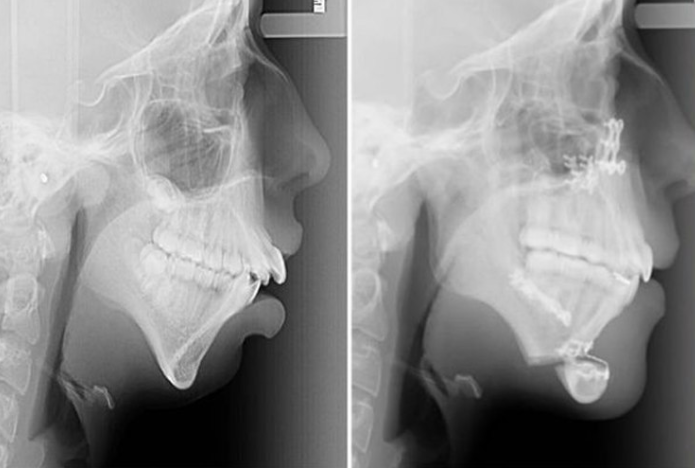

而對(duì)于一些重度的下頦短縮的人,需要配合下頦截骨前移;而下巴退縮嚴(yán)重的一般都有下頜骨發(fā)育不良問題,所以可能要用到牽張成骨正頜手術(shù)。

▼正頜手術(shù)X光照片及效果

終如何選擇,還是先由醫(yī)生診斷再進(jìn)行決定。